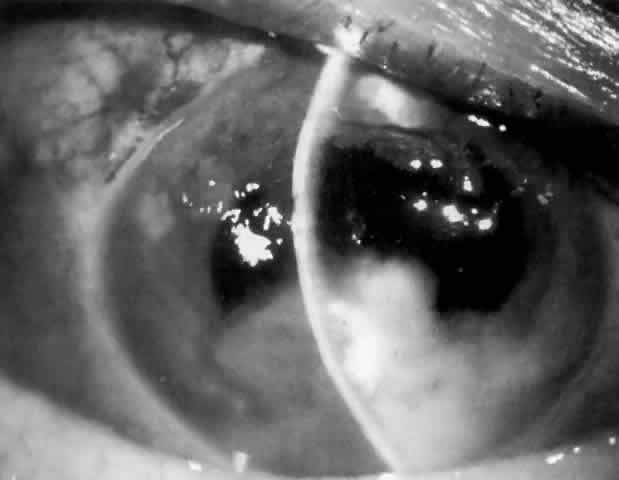

MANAGEMENT. Laser peripheral iridectomy quickly resolves pupillary block (Figs. 6 and 7). Because of inflammation and iridocorneal contact peripherally, this procedure may be difficult to accomplish. If the view is inadequate or a laser is not available, pupillary dilation with phenylephrine will in some cases relieve pupillary block (Figs. 8 and 9). Ultimately the patient will need a laser peripheral iridectomy. If peripheral anterior synechiae have formed or the IOP elevation persists after relief of the pupillary block, the patient will require management similar to that used in chronic angle-closure glaucoma.

Fig. 8. Iris bombé nasal to anterior chamber lens implant before dilation (shadowed area on right). No peripheral iridectomy is present.

Fig. 9. Resolution of pupillary block and iris bombé after pupillary dilation. A subsequent laser peripheral iridectomy was performed.